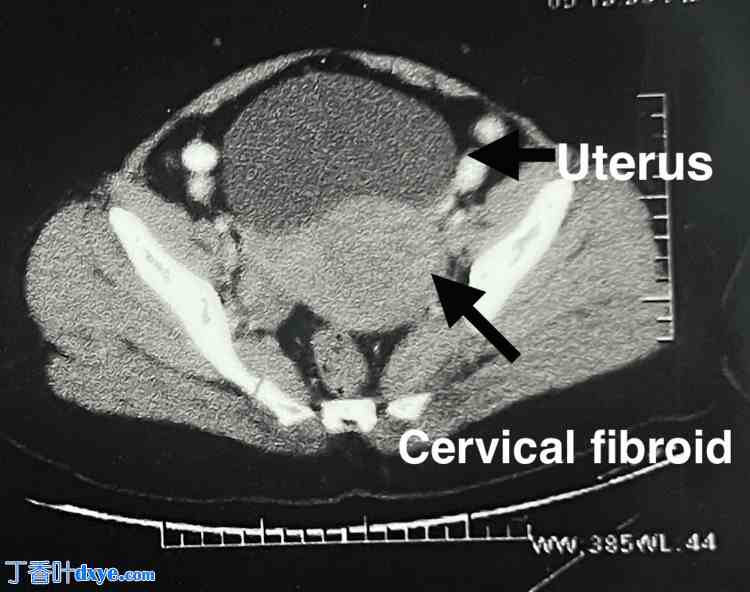

腹部检查未触及肿块。阴道窥器检查发现宫颈前唇有一6厘米大小的无蒂宫颈肌瘤。阴道检查发现宫颈膨出,内含一巨大肿块,宫颈外口向后移位。双合诊检查发现子宫增大。未触及附件肿块。增强CT扫描证实存在一6×7厘米的宫颈肌瘤(图16)。

图16. 腹盆部增强CT扫描显示宫颈肌瘤,大小为6×7厘米。